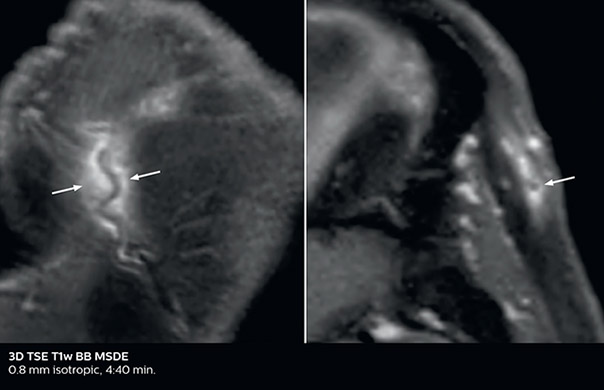

Giant cell arteritis

The 3D TSE T1w black blood MSDE sequence with fat suppression has an isotropic 0.8 mm voxel size and sagittal oblique and axial reformats are made. The images show superficial temporal artery thickening and peri-arterial fat infiltration. The 3D TSE PDw black blood MSDE with fat suppression has 0.55 mm isotropic voxels. The images shows focal involvement of the frontal branch of the superficial temporal artery.

3D TSE T1w BB MSDE

3D TSE PDw BB MSDE

So, what is the actual impact of having more information and more diagnostic confidence? According to Dr. Savatovsky, “One of the indications I’ve seen where using Elition is most impactful is in patients with suspected giant cell arteritis. As an ophthalmologic hospital, we see many patients with suspected giant cell arteritis. Usually we were performing MRI to help us rule out an ischemic stroke, and to verify that the supra aortic vessels are undamaged. With Elition, we still do this, but now we can add on more detailed high-resolution black-blood sequences on superficial arteries. This provides us with high confidence levels for diagnosis of giant cell arteritis (GCA) and as a result, some patients are not sent for a biopsy anymore. A patient who has a normal MRI will not require a biopsy and can be discharged from the hospital in the same day. Before, such a patient would have to stay for about a week, just to find that their biopsy results were negative. We have at least three or four patients a week with suspected giant cell arteritis. For a great deal of these patients we can have a direct impact on their hospital stay.”